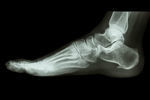

レントゲンなどの局所検査だけでは原因を理解出来ません。

レントゲン、MRI検査などではわからない筋肉や筋膜組織の硬さなどがが原因です。シーバー病の病因や成長期特有の要因に焦点を当てない事があります。

X線やMRIなどの画像検査で骨の異常を診断。症状の身体的要因を重視します。